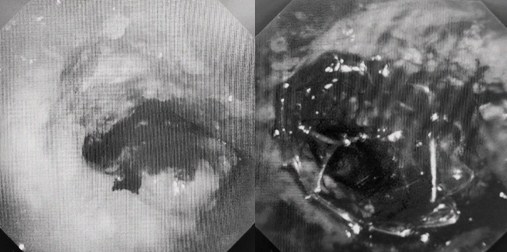

患者入院第二天,在麻醉手術(shù)中心全力配合下,歐陽海峰帶領(lǐng)呼吸介入團(tuán)隊,歷時40分鐘快速置入硬質(zhì)支氣管鏡、鏟切腫瘤,并順利植入全覆膜TTS支氣管金屬支架?;颊邭舛贪Y狀即刻緩解,為患者贏得了寶貴的后續(xù)治療機(jī)會。